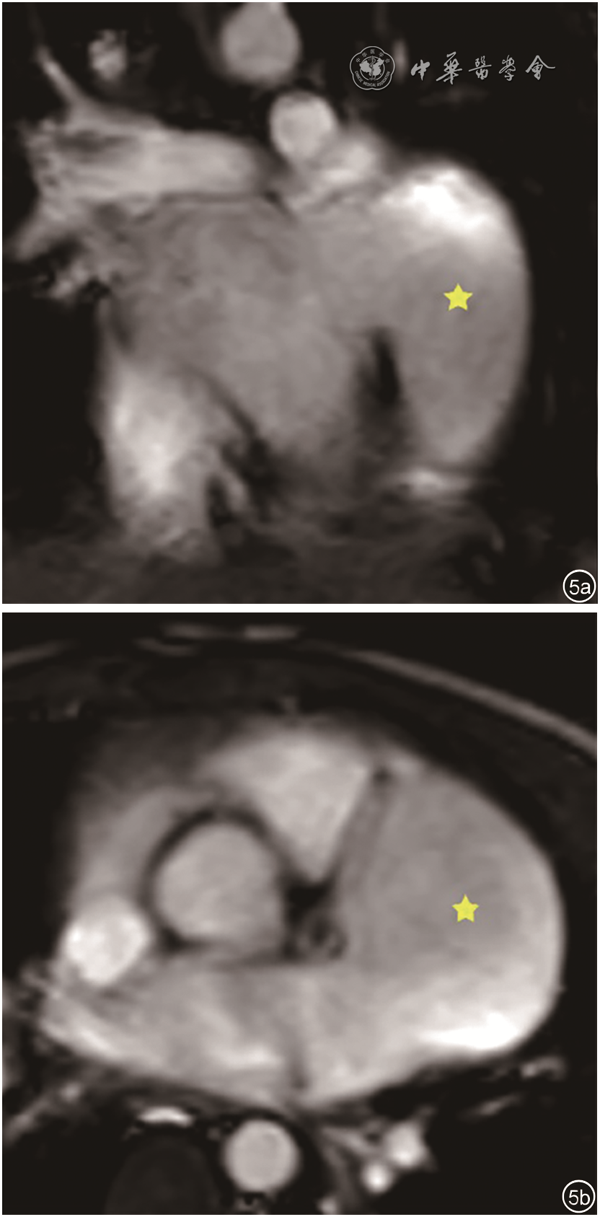

本组病例LAAA内均未见血栓形成,无心包缺损,均为心包内型LAAA。测量LAAA两个径线,长径(32.3±12.9)mm,短径(16.4±6.9)mm。病例1左心室侧壁受压,病例2左心房和左心室重度增大、左心功能减低、二尖瓣中到大量反流,病例4、5合并先天性心脏病,病例6左心房中度增大、二尖瓣中量反流,病例7存在纵隔占位,病例8为肺部肿瘤,病例9存在二尖瓣狭窄伴关闭不全。本组无冠状动脉及肺静脉受压病例。9例患者中1例进行了心脏磁共振成像检查,病例1经心脏磁共振成像证实为LAAA(图5)。

图5 患儿左心耳瘤磁共振心脏亮血序列成像。图a为冠状面显示左心耳瘤(星号所示);图b为横断面显示左心耳瘤(星号所示)